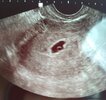

SuperMy już po wizyciejest zarodek

jest też mały krwiaczek, także odpoczywamy